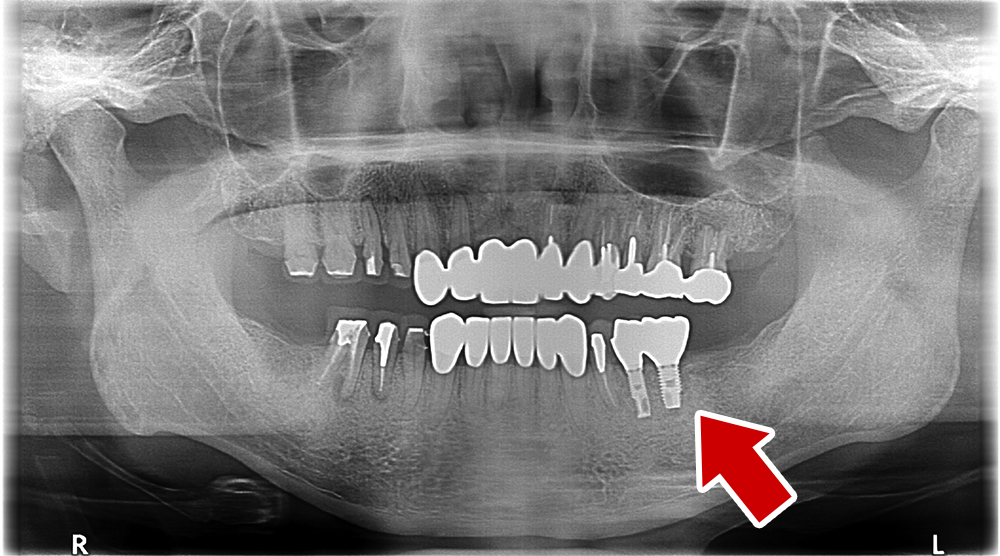

60歳 男性 歯科大学病院 教授からの紹介。ご本人は産婦人科医

- 主訴

- 左下に歯が無くて食事がしずらい

- 処置内容

- 2本インプラント埋入+再生処置。

- 治療費用

- 下顎 約80万円(税込)

- 治療期間

- 下顎:6か月

- リスク

-

術後の腫れ、痛み(ピークは3日後、1週間で軽減)

上部構造物、仮歯の破折、人工歯根脱落リスクがあります

- その他

- 歯科大学病院 教授からの紹介。ご本人は産婦人科医